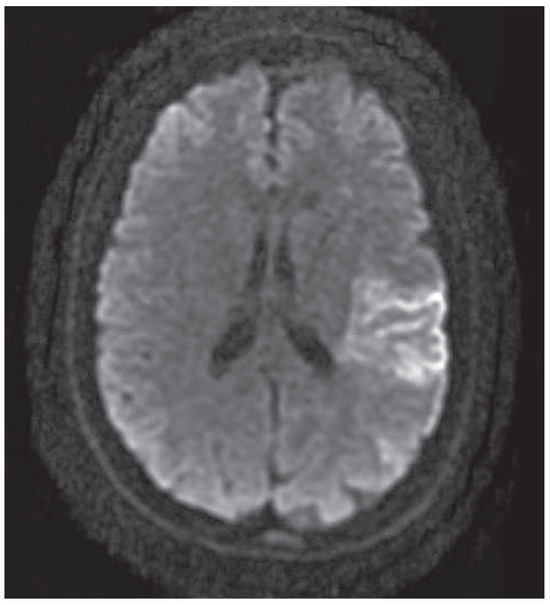

Case Report

Mechanical Thrombectomy After Embolic Internal Carotid Artery Occlusion in Acute Stroke

by Christophe A. Wyss, Anahita Dastoor and Roberto Corti

Cardiovasc. Med. 2014, 17(2), 51; https://doi.org/10.4414/cvm.2014.00204 - 19 Feb 2014

Viewed by 360

Abstract

A 34-year old woman presented to the emergency department with a wake-up stroke, after onset of a sensomotoric paresis of the right arm and motoric aphasia [...] Full article

Show Figures

Figure 1